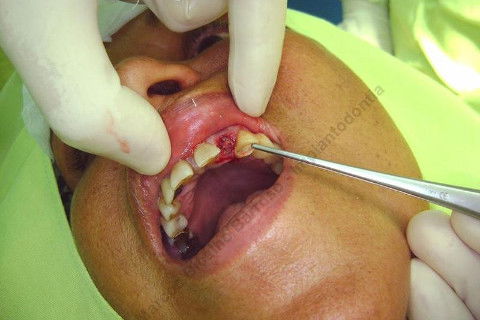

Paciente 66 anos, sexo feminino, procurou meus serviços para instalação de implante e coroa sobre implante na região do dente 22 com fratura radicular. Existem indicações para mais implantes mas a paciente está inrteressada no momento pela resolução deste caso.

Inicalmente estava planejado um implante cone morse 3.5 X 15,0 EX, mas resolvi experimentar um implante HI oferecido pelo vendedor da Bionnovation, como brinde (ele soube que estou preferindo o cone morse mas não trabalham com este sistema), e não consegui carga imediata neste implante. O travamento não foi satisfatório, ficou com um pouco mais de 20 N, menos de 25 N. Apesar desta ocorrência isto não significa que dará problema, apenas não fiz com carga imediata, aguardaremos 4 meses para a osseointegração.

Se o implante utilizado fosse o CM EX 3.5 X 15,0, além deste tipo de implante possuir característica autorosqueante, promovendo pelo seu design um melhor travamento, o seu comprimento de 15mm + 2mm infraósseo, conseguiríamos 6 mm de travamento em osso "virgem" (comprimento da raiz era de 11 mm) e travaria na cortical nasal. Mas este que usei, hexágono interno cônico, fica ao nível do rebordo; o maior que fabricam (comprimento de 15 mm), não apoiou em osso cortical e não é autorosqueante como o EX da Neodent.